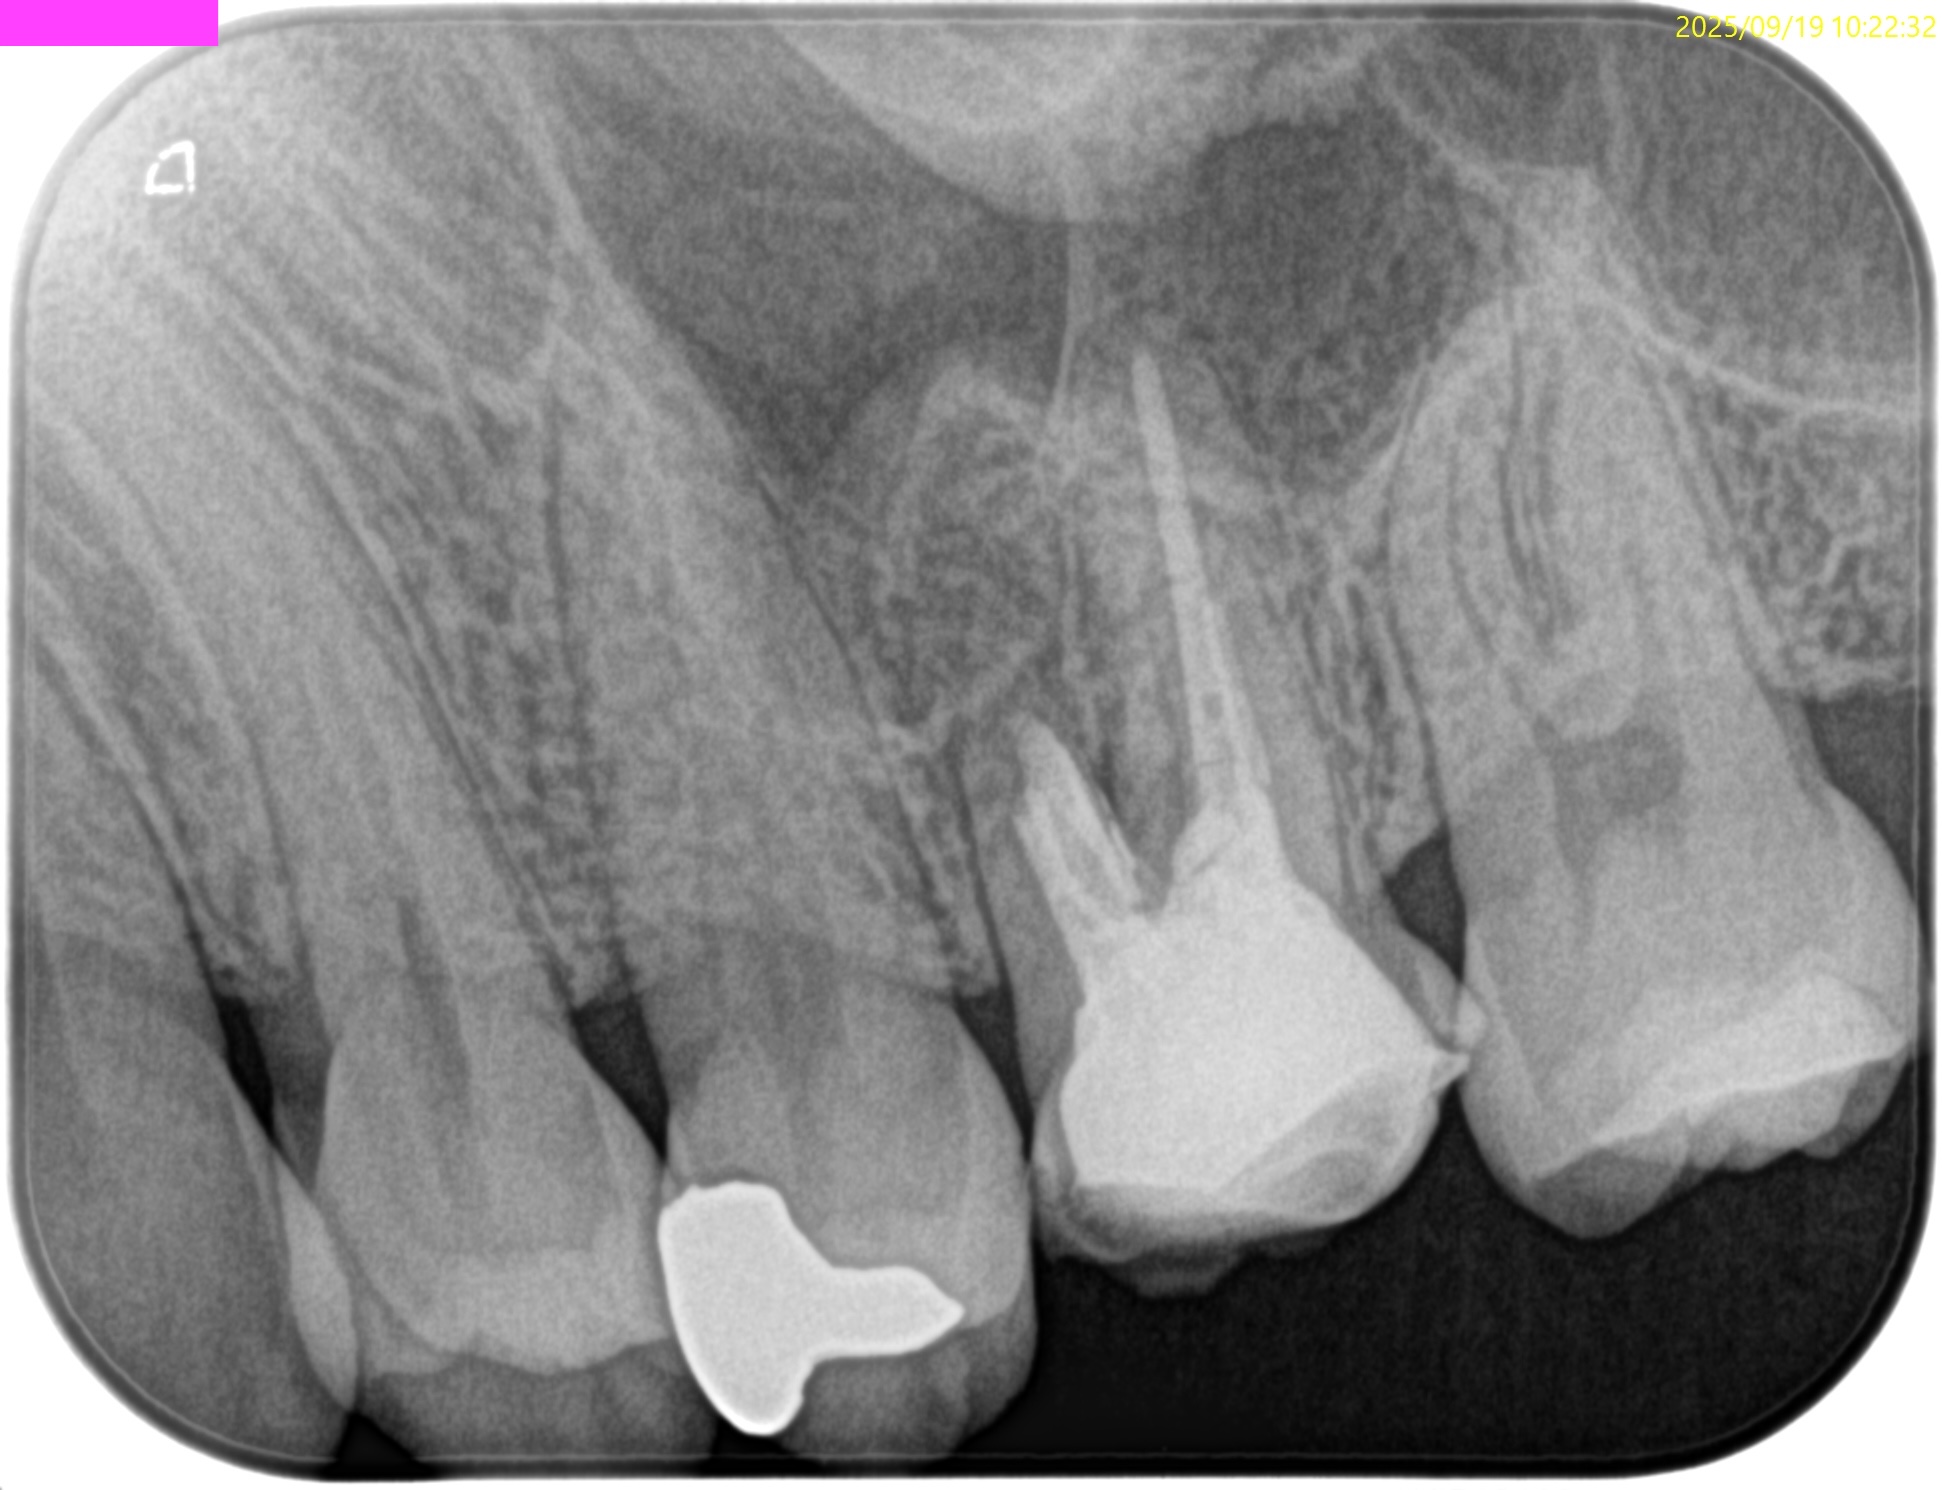

#14 Apicoectomy 4M recall(2025.9.19)

痛みは再現できなかった。

というよりなかった。

術直後と比較した。

大幅に状況が改善している。

治癒が早い人なのだろう。

次回は1年後である。